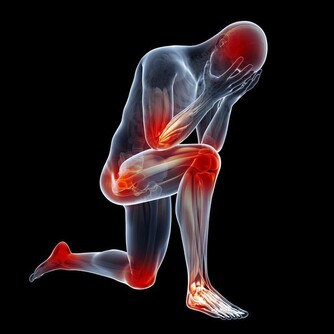

但剩下2/3症狀可能會愈來愈糟(約3成患者會惡化成乾癬性關節炎),

且必須一直持續治療,嚴重的話甚至會無法行走。